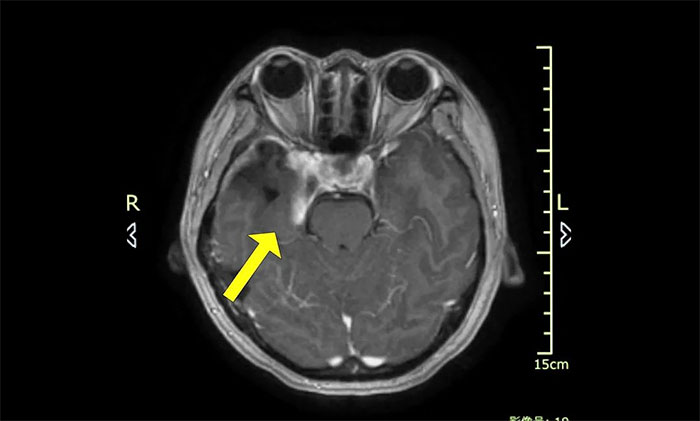

今年初醫(yī)院收治了一位女性患者。該患者因突發(fā)視力模糊,頭暈無法獨(dú)立行走,在外院檢查發(fā)現(xiàn)腦部右側(cè)鞍旁腫塊,手術(shù)病理診斷為海綿狀血管瘤。

▲ 入院時(shí)MRI檢查影像

腫瘤科(放療)頭部伽瑪?shù)督M陳琦主任完善檢查并開展多學(xué)科評估討論,其右側(cè)鞍旁海綿狀血管瘤與視神經(jīng)等重要結(jié)構(gòu)相鄰,若不及時(shí)干預(yù)治療,可因占位壓迫進(jìn)一步加重神經(jīng)功能障礙,甚至導(dǎo)致失明。而該部位病灶的手術(shù)治療難度高、風(fēng)險(xiǎn)大,術(shù)中可能對患者神經(jīng)功能造成嚴(yán)重?fù)p害,應(yīng)考慮采用創(chuàng)傷較小的伽瑪?shù)吨委煛?/p>